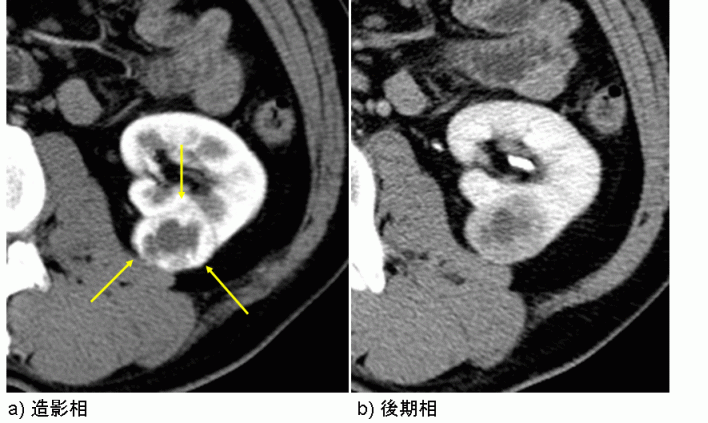

RCC と診断された人の多くは、別の理由で検査を受けた後に診断を受けます。症状が出る前に、超音波検査やCTスキャンで腫瘍が見つかることがあります。

腎細胞がんはどのように診断されますか?

医師は血液検査、尿検査、画像検査を経て腎細胞がんを診断できます。他の種類のがんとは異なり、生検は